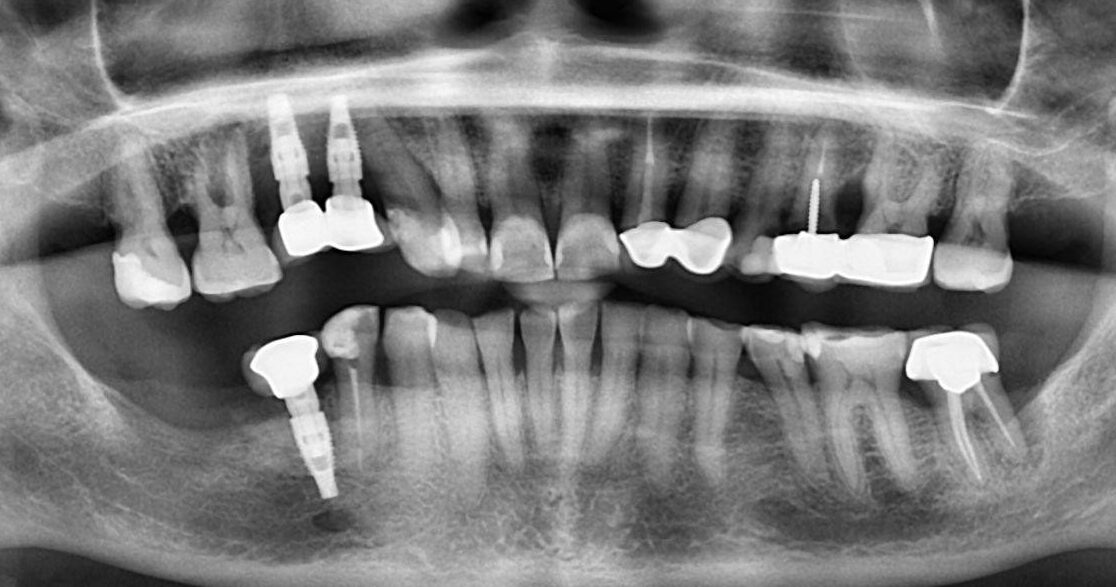

10. What options cannot be selected for the upper jaw of this panoramic X ray?

11. What options cannot be selected for the lower jaw of this panoramic X ray?

12. What option cannot be selected for this panoramic X ray?